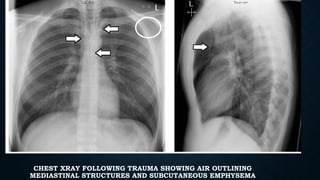

PNEUMOMEDIASTINUM

• Usually from ruptured alveoli

• Can also be from trachea, bronchi,

esophagus, bowel and neck injuries

SIGNS

• Linear paratracheal lucencies

• Air along heart border

• “V” sign at aortic-diaphragm

junction

• Continuous diaphragm sign

CHEST XRAY FOLLOWING TRAUMA SHOWING AIR OUTLINING

MEDIASTINAL STRUCTURES AND SUBCUTANEOUS EMPHYSEMA